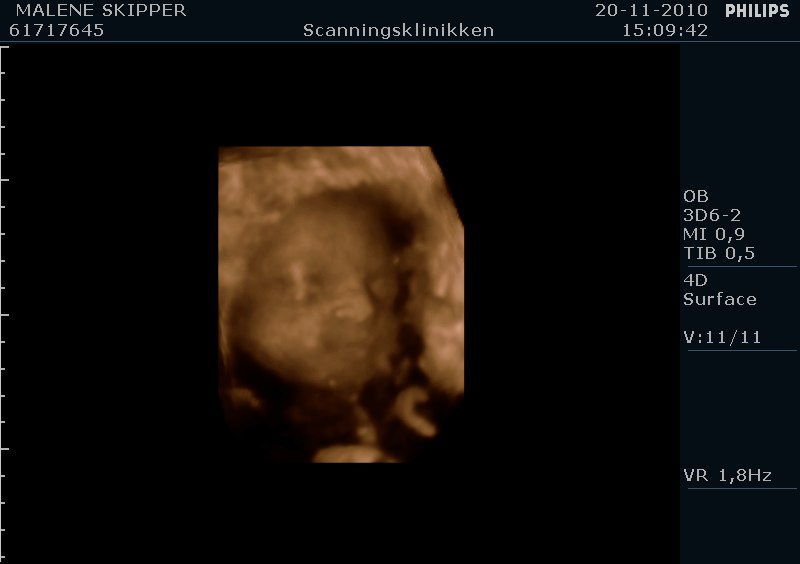

" /> Jeg har været til 4d scanning idag og set vores lille prinsesse som vi er meget stolte af og glæder os til hun kommer ud.. Hun sparker og er livlig hver dag og det er fantastisk..

Her er lige et par billeder fra 4d scanning idag..